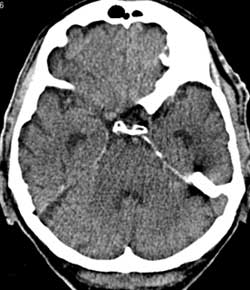

Рис. 7. Влияние коллимации и толщины среза на качество изображений на примере исследования головного мозга. Во всех случаях коллимация 1 мм. (Слева) Реконструированная толщина среза 1 мм. (В центре) Толщина среза 4 мм. (Справа) Толщина среза 8 мм. На изображении (Слева) на область варолиевого моста накладываются артефакты от пирамиды левой височной кости. На изображениях (В центре) и (Справа) они практически отсутствуют - эффект усреднения, однако при толщине среза 8 мм (Справа) нечетко визуализируется ликворное пространство над правой гемисферой мозжечка по той же причине. Толщина среза 4 мм в данном случае оптимальна.